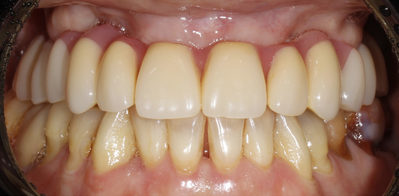

Результат лечения:

В результате мы восстановили надёжную опору для несъёмного протеза - конструкция стабильно фиксируется даже при выраженном дефиците костной ткани. Пациентка снова может полноценно жевать и улыбаться без стеснения, при этом удалось обойтись без длительной костной пластики и синус-лифтинга. Через полгода мы планируем заменить временный протез на постоянный.